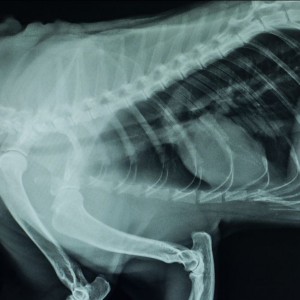

High-flow nasal oxygen (HFNO) therapy is a non-invasive respiratory support method that provides oxygen-enriched, warmed, and humidified air to respiratory-compromised patients. It is widely used in...